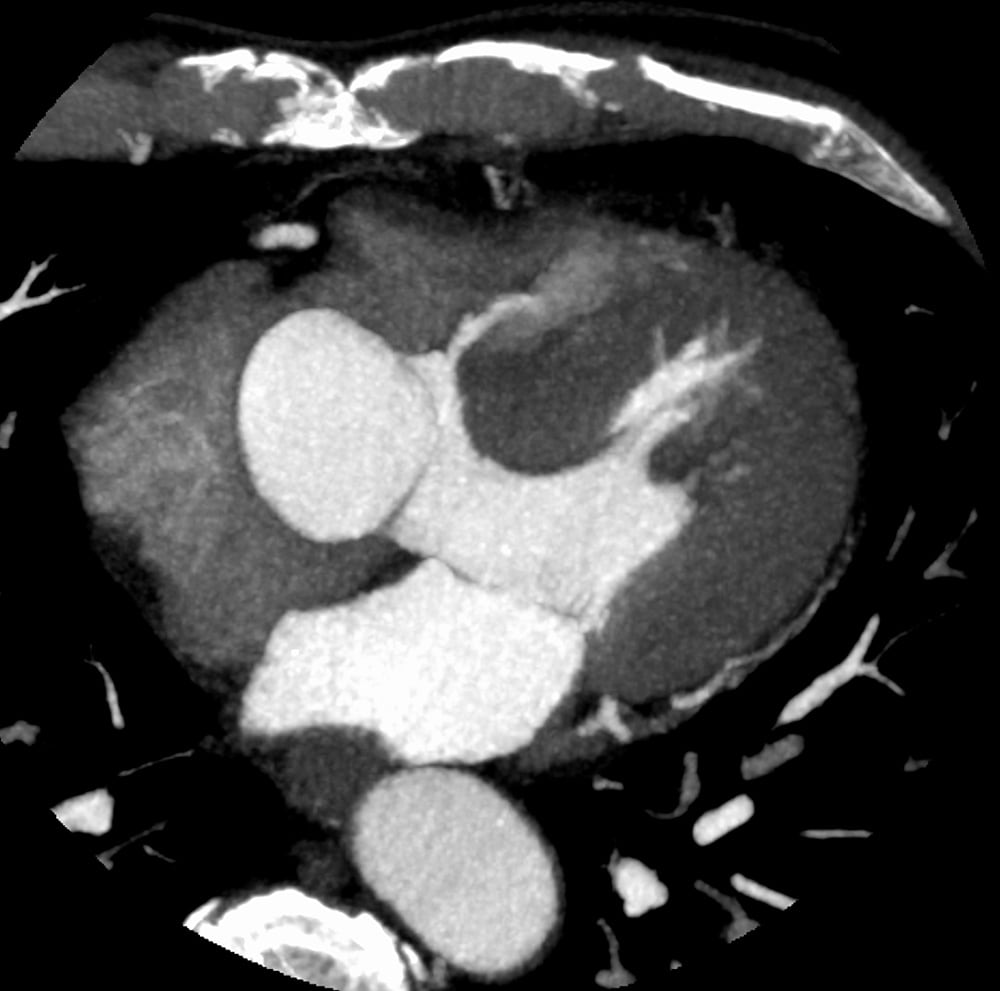

図3.心臓CT MIP axial画像(収縮末期)

膜様部心室中隔に欠損を認め、造影剤が左室から右室へ流入している。